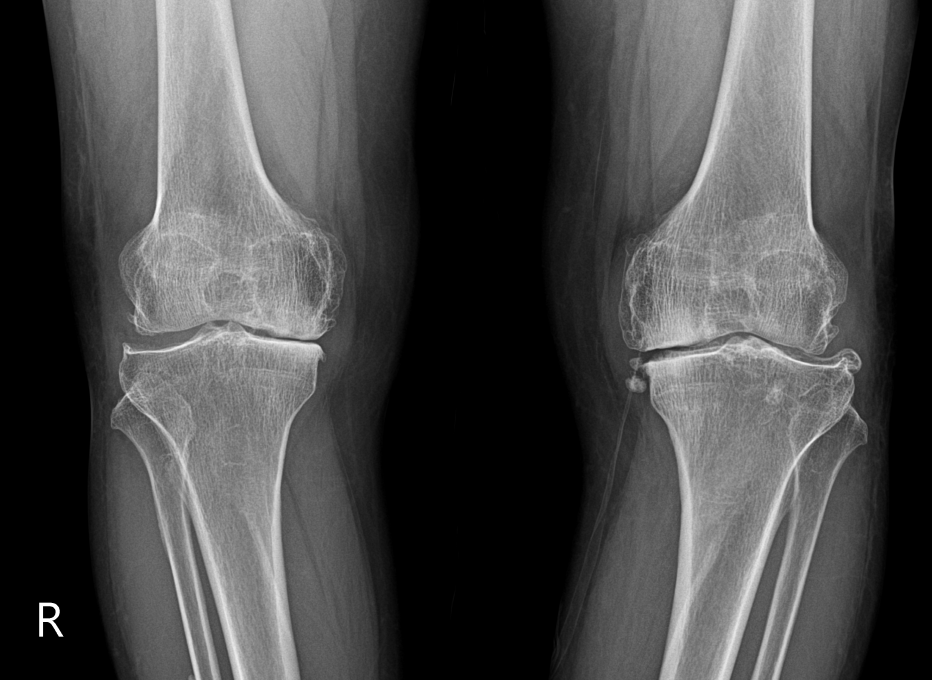

슬관절(무릎관절)의 퇴행성 관절염

1. 특징

- 골관절염의 호발부위

2. 원인

- 고령, 슬관절 병변 손상

- 비만증, 내반슬, 외반슬 등 기계적 부하축의 이상

- 무리한 노동, 부적절한 자세가 원인이 되기도 합니다.

3. 임상증상

- 동통과 이상음, 심한경우 운동제한, 근위축

4. 방사선학적 소견

- 초기에는 정상소견이나, 점점 관절간격이 좁아집니다.

- 진행된 질환은 관절면의 가장자리에 골극을 형성합니다.

5. 퇴행성 관절염의 병리학적 변화

- Cartilage Loss, Osteonecrosis, Osteoporosis, Osteophyte

- 무릎 안쪽의 Joint space가 좁게 나타난 것을 확인할 수 있습니다. 퇴행성 관절염이 진행되고 있는 모습입니다.